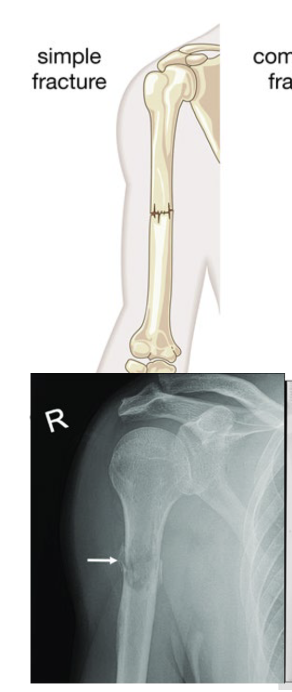

What are the main 2 types of fractures?

Simple And Compound open

What is a simple fracture?

Fx where bone does not break through the skin

What is a compound fracture?

Portion of the bone protrudes through the skin

What type of fracture is this?

Avulsion